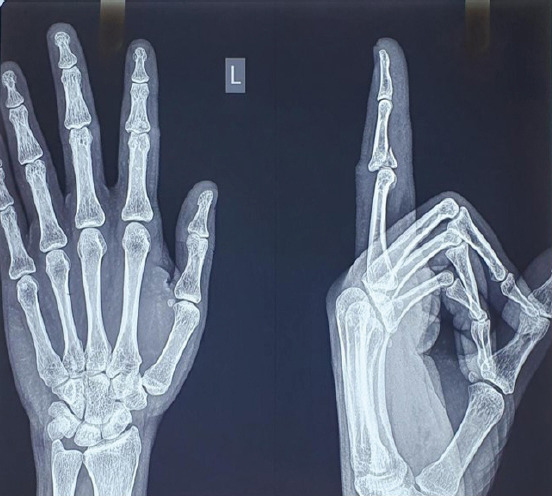

Case report: A 37-year-old male sustained an intra-articular middle phalanx base fracture with dorsal subluxation of the left index finger during a cricket injury. Examination showed swelling, tenderness, and a flexion deformity. Radiographs confirmed a comminuted volar lip fracture. Under fluoroscopic guidance, a Suzuki frame was applied using three K-wires and rubber band traction. Advanced imaging was not deemed necessary for acute management. Early active motion was initiated post-operatively, followed by a structured hand therapy protocol. At 6 months, radiological union, >90% range of motion, minimal pain, and return to function were achieved.